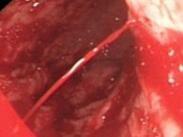

上消化道出血

• 上消化道出血

628健康網為您分享有關上消化道出血的癥狀,上消化道出血的治療方法,上消化道出血的預防知識,上消化道出血的癥狀圖片,上...